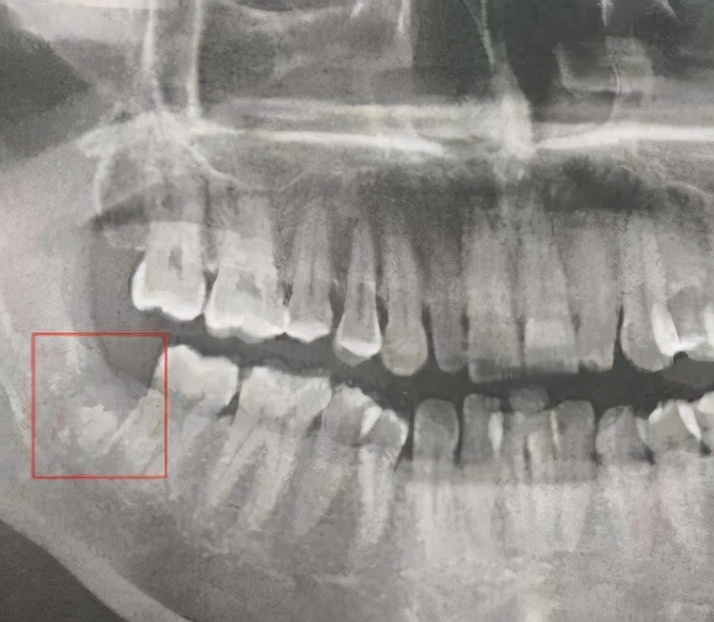

“干槽症”为复杂牙拔除后出现的并发症,表现为拔牙窝干燥、空虚、无渗出物,伴随剧痛的情况,也有人管它叫“牙槽炎”、“牙槽窝坏死”、拔牙后骨髓炎综合征等。

发生率:下颌阻生智齿拔除后>下颌第三磨牙>下颌第一磨牙>下颌第二磨牙,别的牙很少见,前牙发生率最低。

拔牙后,牙根原来所在的牙槽窝,应该由血凝块充满而后渐渐愈合,由于种种原因导致拔牙后2~4天牙槽窝内血凝块分解、破坏、脱落、感染而导致拔牙窝骨壁暴露并发生多处小的骨质坏死灶,可出现碎小的死骨。